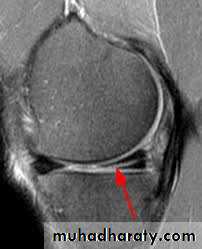

MRI

is reliable method of diagnosis,